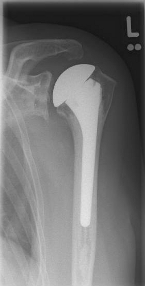

left: X-ray image of an omarthrosis

right: X-ray of a healthy shoulder joint